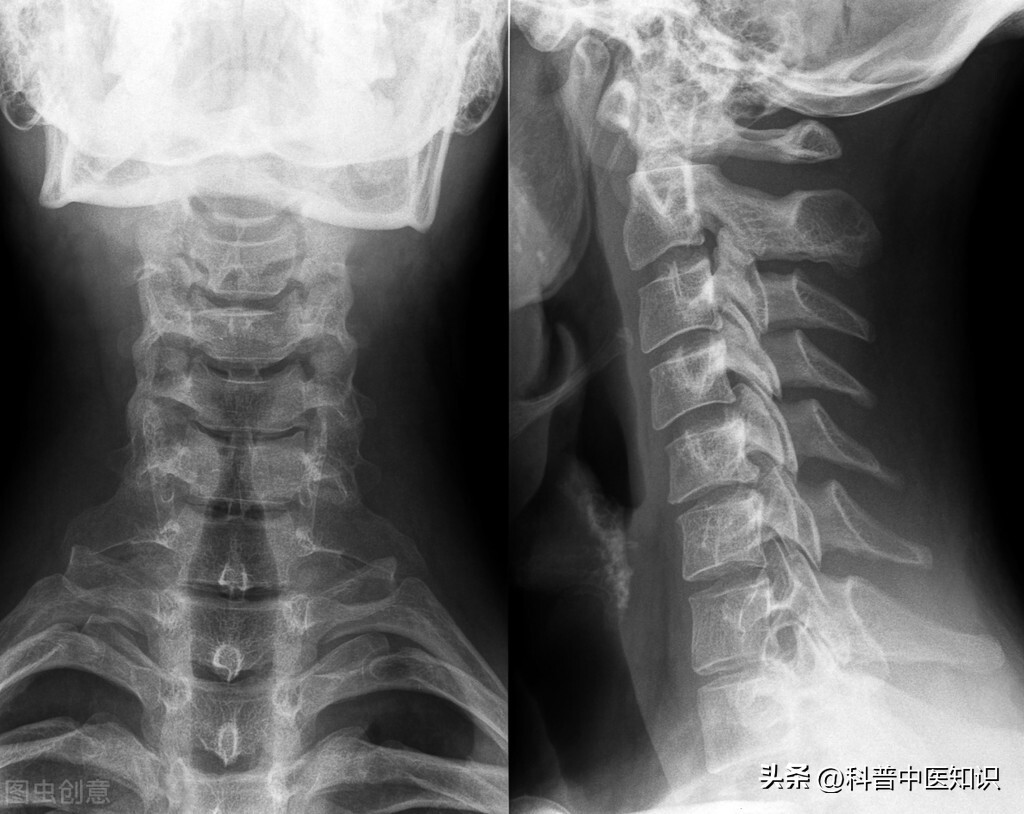

强直性脊柱炎过去被认为是类风湿关节炎的一个临床类型。后来发现,HLA-B27阳性的人群易患此病,证明了本病是一个独立的疾病。本病起病迟缓,以持续性腰或涉及胸、颈段脊柱疼痛,晨僵,活动受限,甚则出现驼背、脊柱强直、骶髂关节受损,两腿活动受限等,为主要症状的疾病。强直性脊柱炎的发病男性多于女性,且易多见于15—40岁左右的青少年及中年人。实验室检查90%以上的患者HLA—B27阳性。X线拍片显示:骶髂关节融合。对强直性脊柱炎的治疗,焦树德教授有自己独特的见解。

焦老还十分注意引经药的应用,对不同部位的疼痛,应用不同的药物引药物直达病所。如膝关节疼痛肿大,可用川牛膝、泽兰、桃仁配合应用,去死血,生新血;如颈部强硬,可用葛根引药到颈;如肩膀疼痛,可用片姜黄活血化瘀,除肩痛;如强直性脊柱炎与胃病疼痛合见,可用苍术、厚朴、千年健等,既可以治疗风湿又可以不伤脾胃,一举两得。